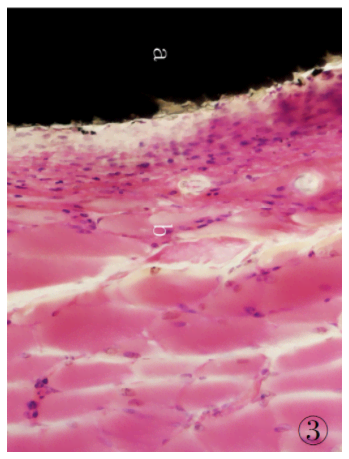

1.3.9 組織切片的染色將組織切磨片經(jīng)蒸餾水充分清洗后,參照文獻[5]的方法進行染色:蘇木精染液30 min,自來水充分沖洗,1%鹽酸乙醇分化30s,流水沖洗后再入溫水返藍(lán),置伊紅染液5min,自來水沖洗,待組織切片自然干燥后經(jīng)Technovit 7210VLC封片,光鏡下觀察。制得的組織切片經(jīng)HE 染色后,細(xì)胞核、細(xì)胞質(zhì)著色對比鮮明,組織細(xì)胞形態(tài)清晰,可直接在光學(xué)顯微鏡下進行組織學(xué)觀察,可見植入的CF/PEEK 復(fù)合材料與周邊肌肉組織結(jié)合緊密( 圖2、3) ,植入的復(fù)合材料周圍可見新生纖維結(jié)締組織,纖維囊壁結(jié)構(gòu)已形成。

圖3 高倍鏡下埋置有CF/PEEK 復(fù)合材料的肌肉組織病理切片:a.試驗樣品CF/PEEK復(fù)合材料; b.肌肉組織